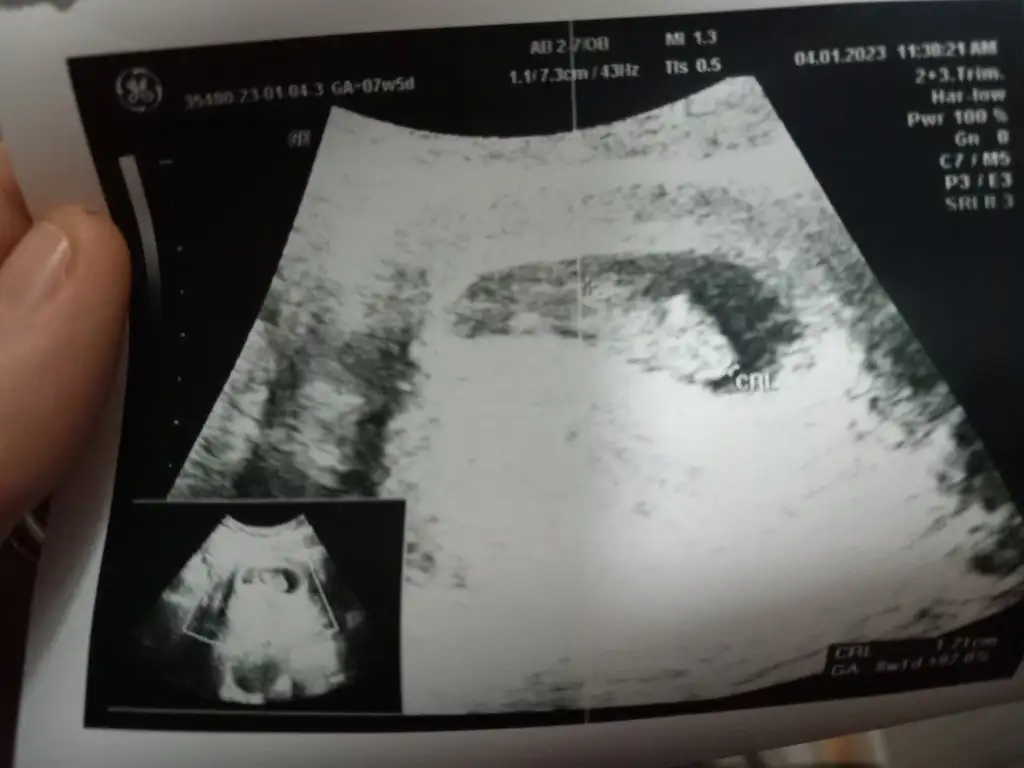

6-9 haftalık fotosunu atarsanız yaparım burda bebişiniz çok büyük böyle bilemiyorum maalesefBanada bakar mısınız lütfenn 12 haftalik tam

Karından ultrasonmuEki Görüntüle 3202132 bana'da bakarmisiniz 9 haftalık

6-9 haftalık fotosunu atarsanız yaparım burda bebişiniz çok büyük böyle bilemiyorum maalesef burda 7 hafta 5 günlük

Heh işte böyle fotolar lazım banaEki Görüntüle 3202507 Ya da bu var

Her türlüsü mevcut fotoların da işte ben de ah bi anlasamHeh işte böyle fotolar lazım banaKız gibi geldi canım bana karından ultrasonsa eğer